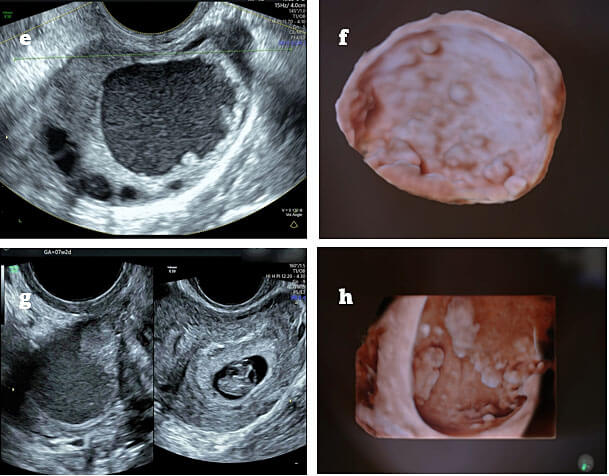

تحسن واضح في التبويض عند متابعة السونار.

الكثير من النساء يروين أن أول دورة علاجية كانت مليئة بالتوتر، لكن مع رؤية البويضة تكبر على شاشة السونار، يبدأ الأمل يكبر معها. حجم البويضة عندما يصل إلى 18–22 ملم يكون مؤشرًا قويًا على قرب التبويض، وهنا تتجدد المشاعر ويبدأ العد التنازلي لأجمل خبر قد يغير الحياة بالكامل.

ظهور بويضات بحجم مناسب في السونار.

أما الاطمئنان فيبدأ عندما نرى استجابة واضحة في السونار، وعندما تتحسن الدورة الشهرية، وعندما يخبرنا الطبيب أن حجم البويضة ممتاز وأن بطانة الرحم مناسبة. هذه مؤشرات قوية أننا نسير في الطريق الصحيح.

السونار المتكرر لمتابعة حجم البويضات.

متابعة سماكة بطانة الرحم.